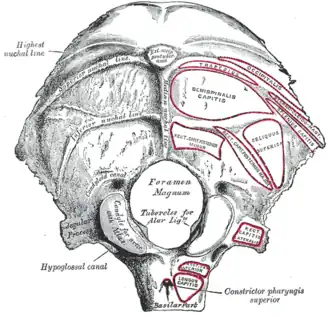

Occipital bone. Outer surface.

Occipital bone. Outer surface.